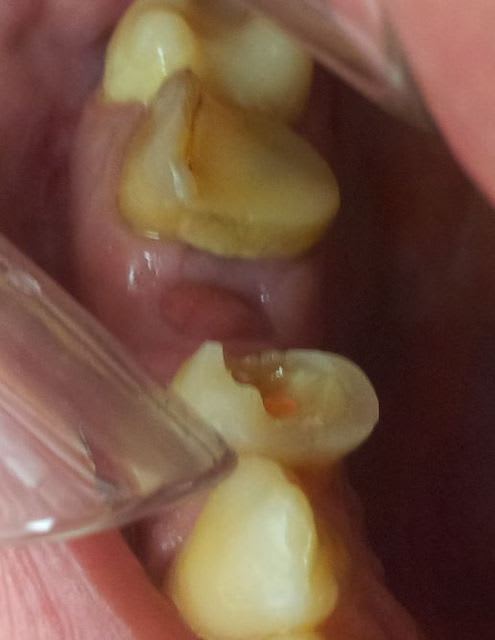

Mais l'alvéole de 25 ne me plait pas: bourgeonnement, et sur la radio on voit encore bien la lamina dura de l'alvéole .

Je pense aller regratter tout ça....qu'en pensez-vous?

je ne vois pas bien sur la photo.

ça n'a pas l'air infectieux.

mais sur la radio, il y a une proximité sinusale évidente.

vérifie qu'il ne s'agit pas d'un bourgeonnement de la muqueuse sinusienne (ça m'étonnerait, mais il faut y penser)

Bon, à 5 semaines ça n'a rien de très alarmant. Ca me fait penser à une extraction où le patient est reparti avec son alveole vide ( sans eponge et sans suture), a fait des rinçage, et/ou à cracher ou d'autre betise dans ce genre dans la demi journée qui a suivi, avec un caillot qui a eu du mal à s'installer. D'ou retard à la cicatrisation.

S'il n'y a pas d'infection, je n'irai pas perturber les osteoblastes qui commence à faire leur boulot.